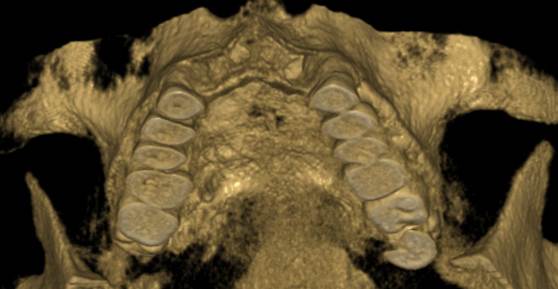

Je speciální zubní digitální tříprostorový tomograf (3D), který umožňuje na základě jediného snímkování vytvořit všechny typy RTG zobrazení, které jsou pro lékaře potřebné. Díky používané technologii tzv. „kuželového paprsku“ a speciálním senzorům je výrazně zmenšená dávka záření - o více jak 80% proti klasickému CT vyšetření. To je významné zejména u dětí. Pomocí tohoto přístroje je možné zjisti skutečnou situaci v čelistních kostech pacienta tedy množství kosti - můžeme změřit skutečnou šířku i výšku kosti, i kvalitu kosti (hustotu) v místě uvažované implantace. 3D (tříprostorové) zobrazení umožňuje zvýšit prostorovou představu operatéra ještě před vlastní operací a zároveň pacientovi lépe objasnit a ukázat oblast plánovaného zavedení implantátu.

Pacient „neumí číst“ RTG snímky, ale díky 3D zobrazení vidí „svoji skutečnou čelist“ - např. jak je nízká či úzká, vidí průběh nervu nebo velikost čelistní dutiny, což mu umožní i pochopení nutnosti v některých případech provést pomocné zákroky ještě před vlastním zavedením implantátu (viz. kostní štěp, sinus lift, kostní granulát...).

Vyšetření pomocí tohoto přístroje používáme i ve stomatochirurgii (zlomeniny čelistí, zuby moudrosti, cysty, onemocnění čelistního kloubu), ortodoncii (retinované zuby, nadpočetné zuby), parodontologii atd.